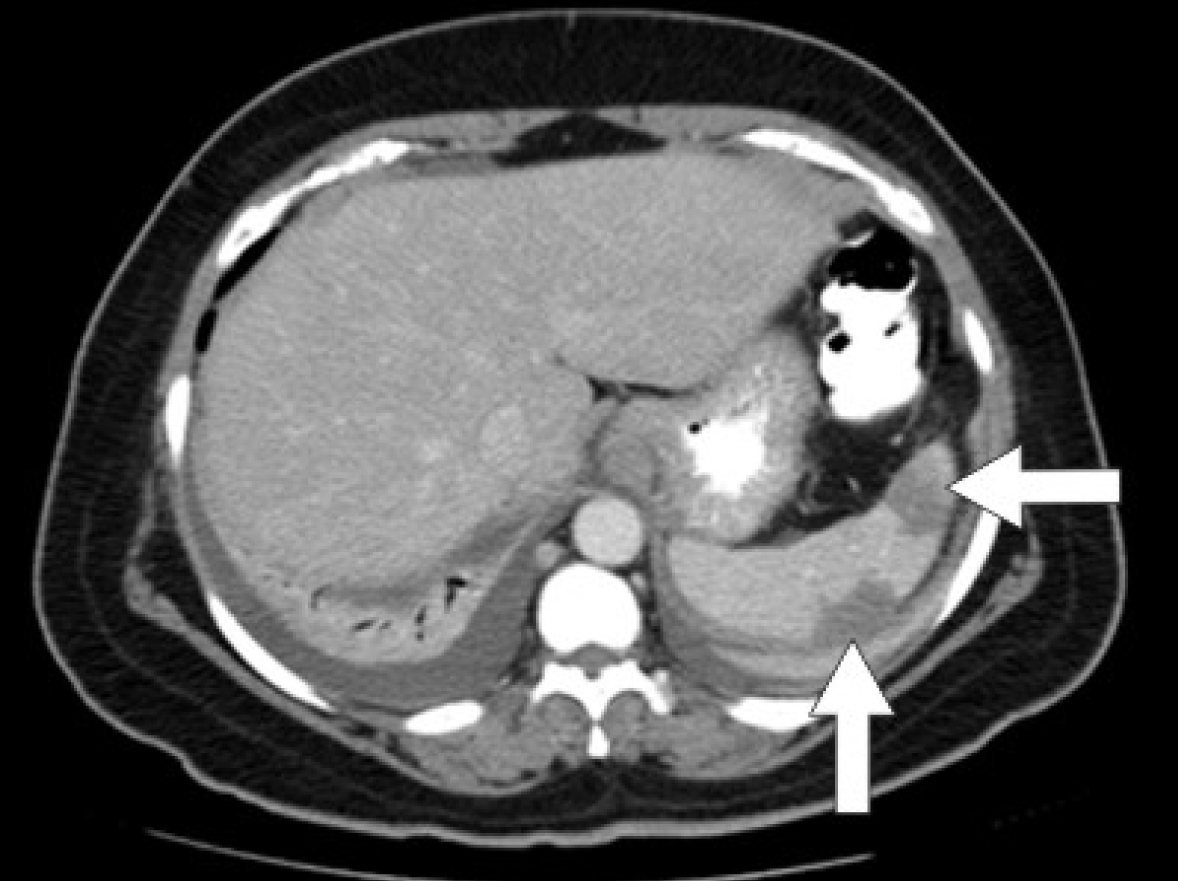

Initial laboratory studies were as follows: WBC 15.47 x 10/mcL, with a neutrophil count of 11.7 x 103/mcL; hemoglobin 13.3 gm/dL; platelet count 33 x 103/mcL; troponin 4.02 ng/mL; total CK 96 ng/mL, with a CK-MB 2.7 ng/mL and a relative index of 2.5; creatinine 0.8 mg/dL; international normalized ratio (INR) 1.56; PT 18.6 second; PTT 34.6 second; fibrinogen 209 mg/dL; fibrin degradation products (FDP) > 20 mcg/mL, and CA125 of 114 U/mL. Urinalysis showed moderate blood. Her EKG showed findings consistent with an acute, non-ST elevation myocardial infarction. CT imaging showed numerous large splenic, wedge-shaped hypodensities (Fig. 1) with similar areas in the kidneys bilaterally (Fig. 2), most consistent with infarcts. Also noted was a 12.4 x 8 x 11 cm right pelvic, complex, cystic and solid appearing mass (Fig. 3). An echocardiogram was obtained and showed mild mitral regurgitation and a moderate sized vegetation on the anterior mitral valve leaflet (Fig. 4). Lower extremity Duplex showed no apparent thrombosis.

![]() Click for large image | Figure 1. CT scan of the abdomen showing large splenic wedge-shaped hypodensities consistent with splenic infarcts. |